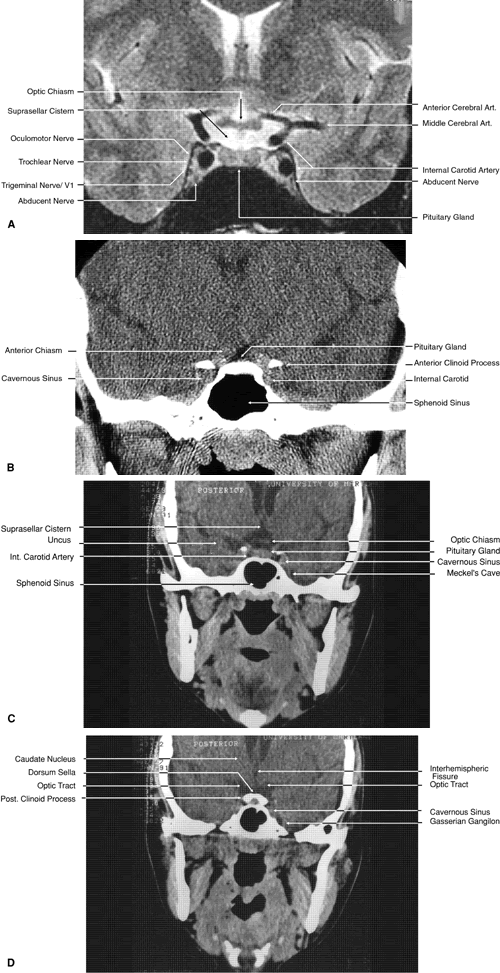

The globe is shown in Figure 12. The orbit and periorbital structures are shown in Figures 13 through 16, and the optic canal is shown in Figures 17 through 26. The cavernous sinus and optic chiasm are shown in Figures 27 and 28, and the posterior visual pathway and cranial nerves are shown in Figures 29 through 33.

Fig. 27. Coronal images through cavernous sinus and optic chiasm. A. T1-weighted magnetic resonance imaging through anterior chiasm. B. Computed tomography image through anterior chiasm. C. Computed tomography image through posterior chiasm. D. Computed tomography image through optic tract.

Fig. 28. Axial computed tomography image with contrast medium through cavernous sinus and pituitary gland.